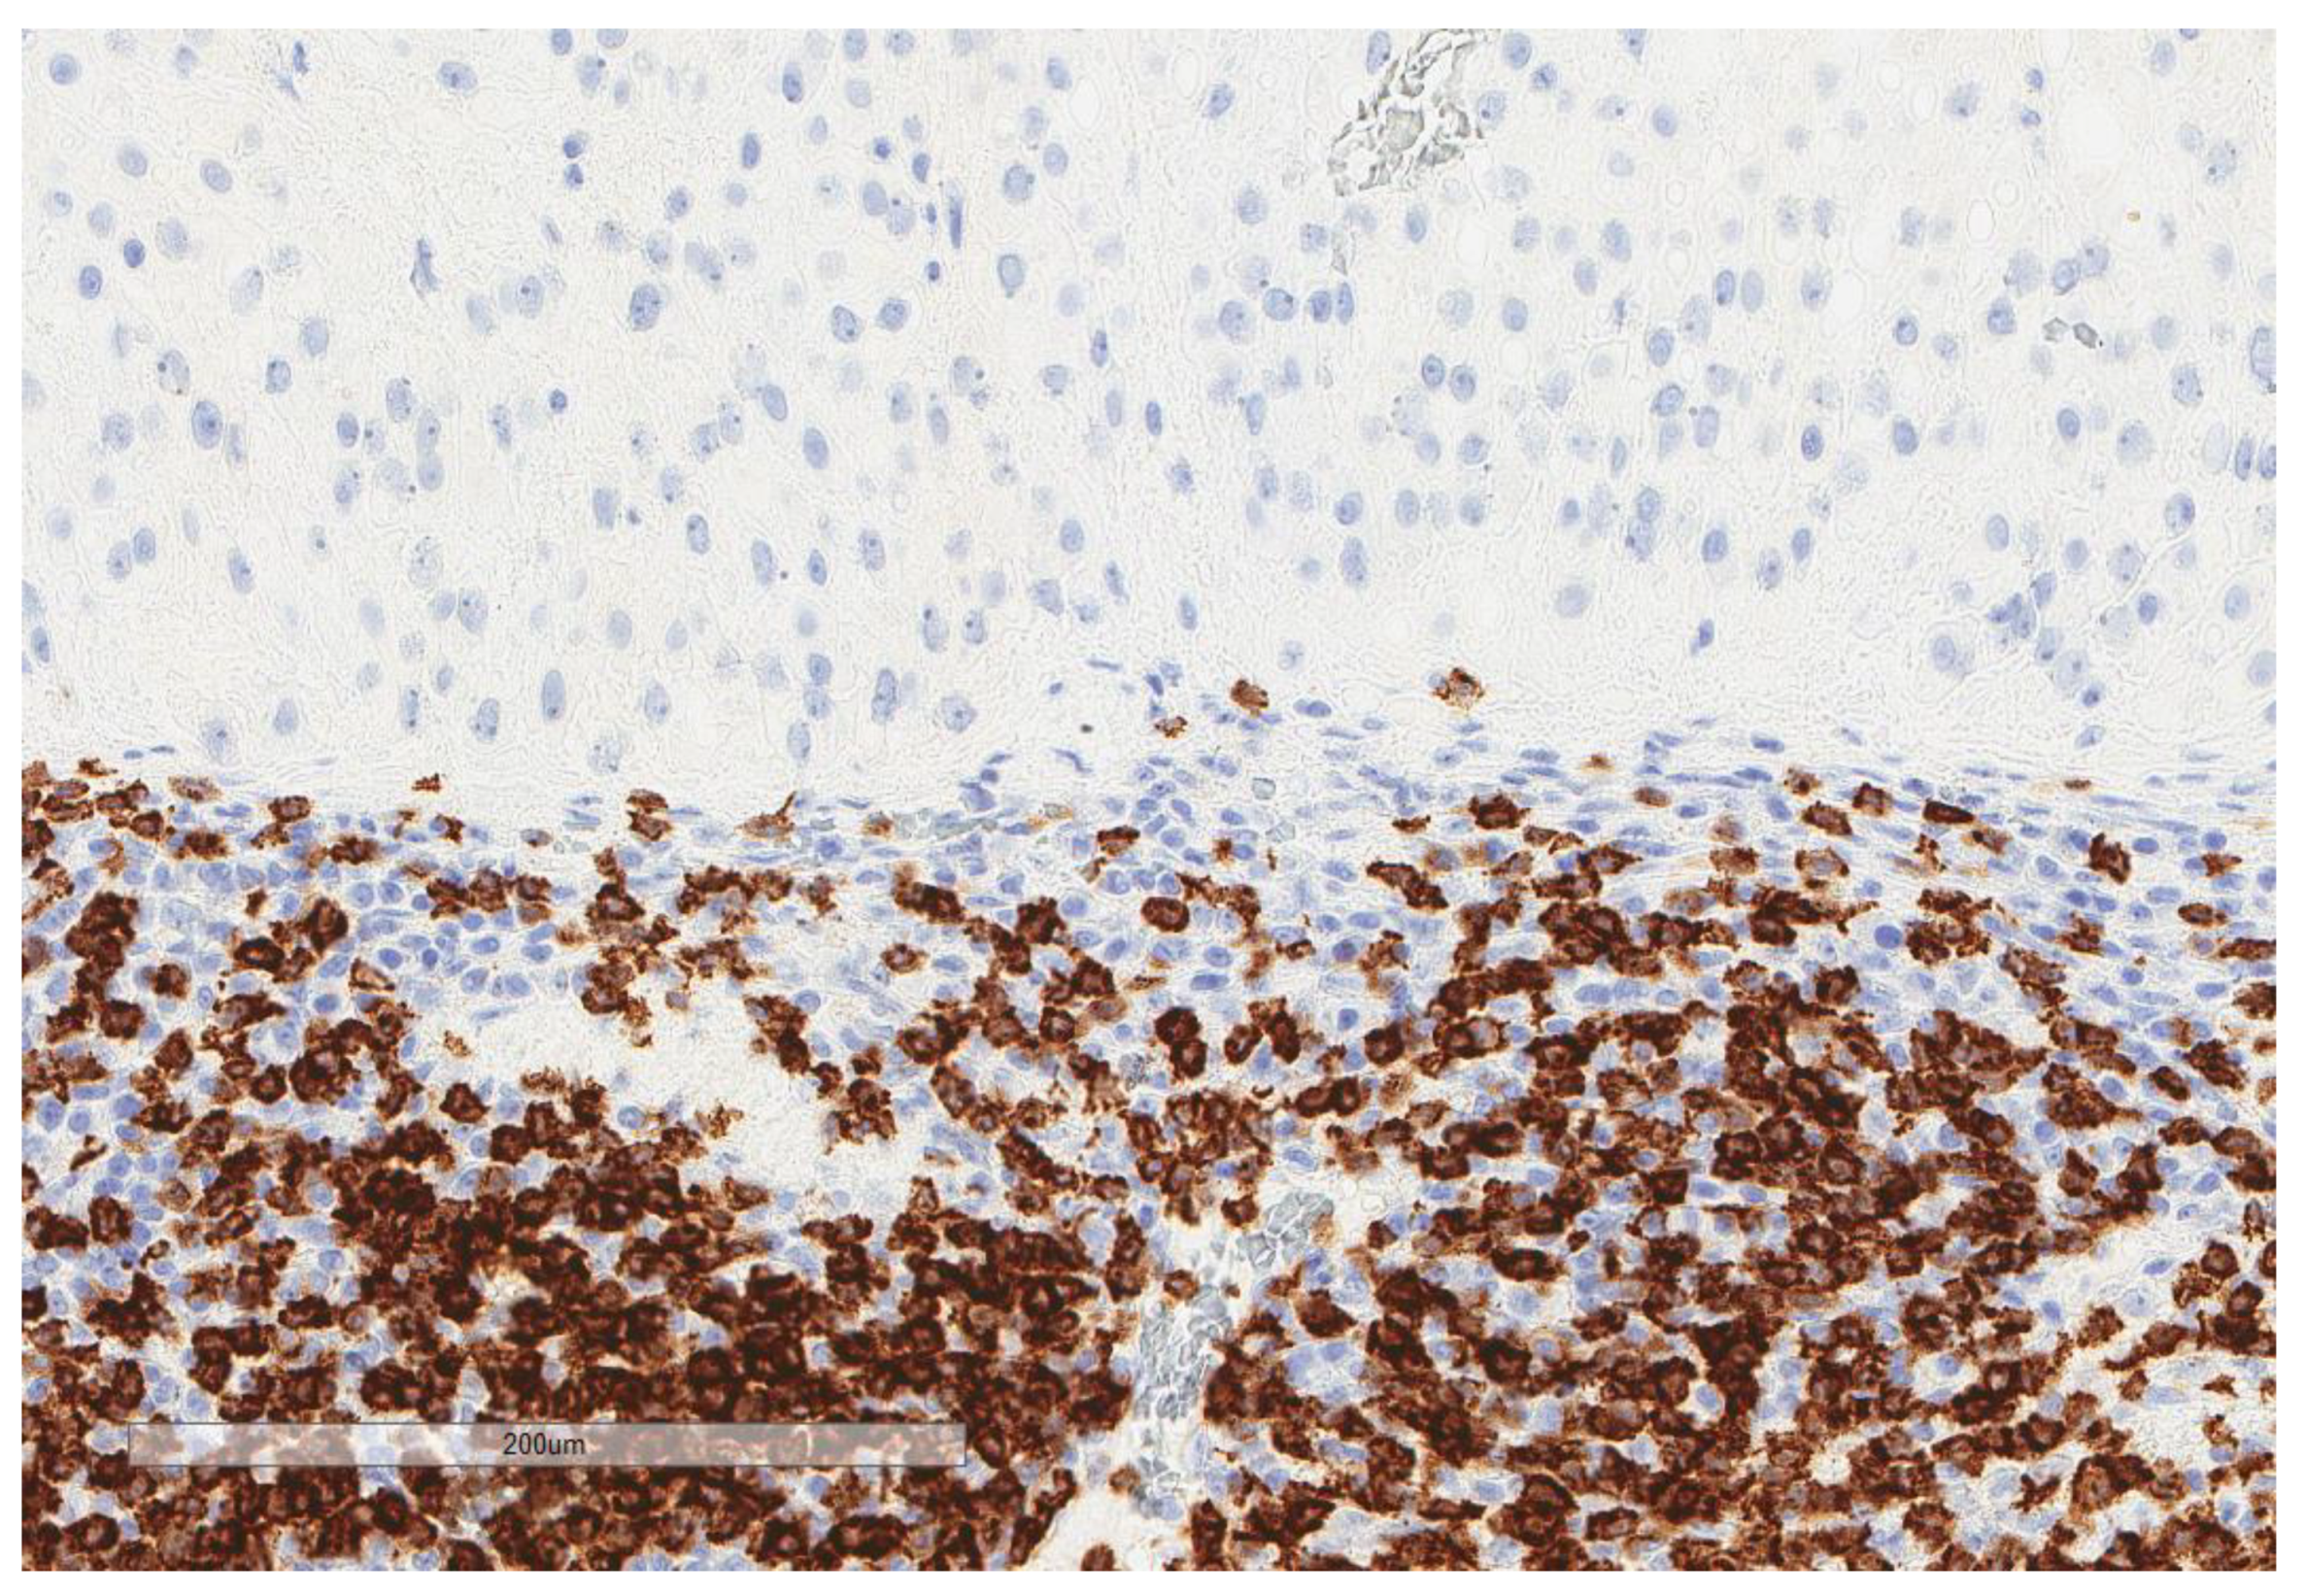

| CD20 (n = 73) | |

| Low (score 0–1) | 65, 89% |

| High (score 2–3) | 8, 11% |

| CD8 (n = 81) | |

| Low (score 0–1) | 55, 67.9% |

| High (score 2–3) | 26, 32.1% |

| CD163 (n = 74) | |

| Low (score 0–1) | 45, 60.8% |

| High (score 2–3) | 29, 39.2% |

| PD-L1 inflammatory cells (n = 81) | |

| No (score 0) | 60, 74% |

| Yes (score 1–3) | 21, 26% |